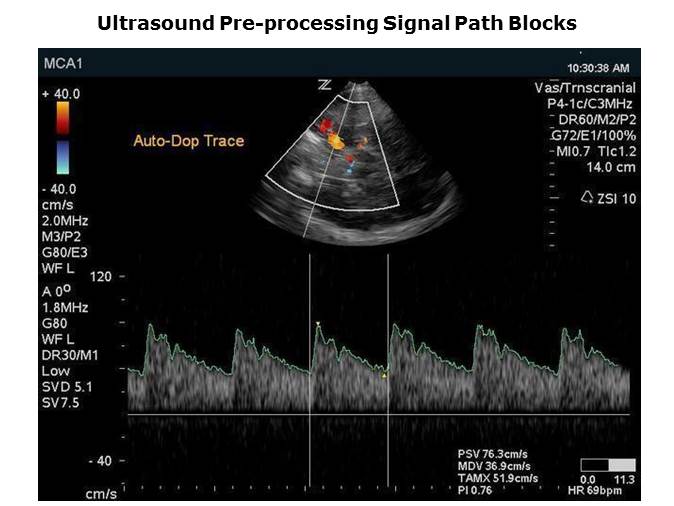

The image on this slide is a blowup of the picture in the previous slide. The Spectral Doppler is the lower image and the B-mode is the image above and the color is the color flow overlay on top of the B-mode image. Looking at the Doppler image at the bottom, the scrolling spectral display indicates flow velocity on the X axis while the Y axis is time. The intensity of the image shows the strength of the flow of blood.